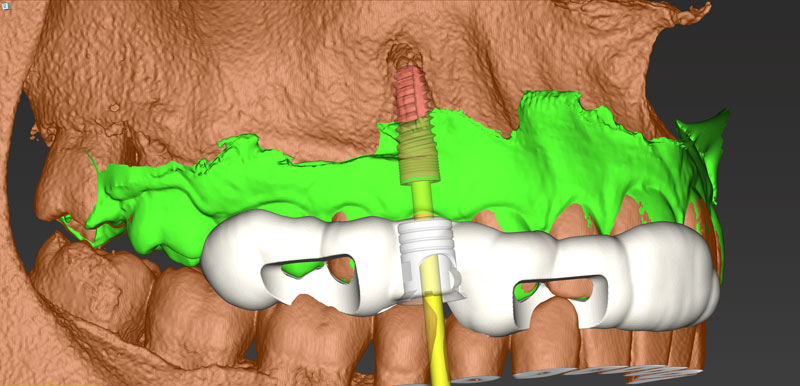

Ψηφιακό πλάνο θεραπείας

Κατευθυνόμενη τοποθέτηση εμφυτευμάτων

Είδη και ακρίβεια χειρουργικού οδηγού

Σχεδιασμός χειρουργικού οδηγού

Κατασκευή χειρουργικού οδηγού στο ιατρείο (3d printing)

- Ψηφιακό πλάνο θεραπείας

- Κατευθυνόμενη τοποθέτηση εμφυτευμάτων

- Είδη και ακρίβεια χειρουργικού οδηγού

- Σχεδιασμός χειρουργικού οδηγού

- Κατασκευή χειρουργικού οδηγού στο ιατρείο (3d printing)